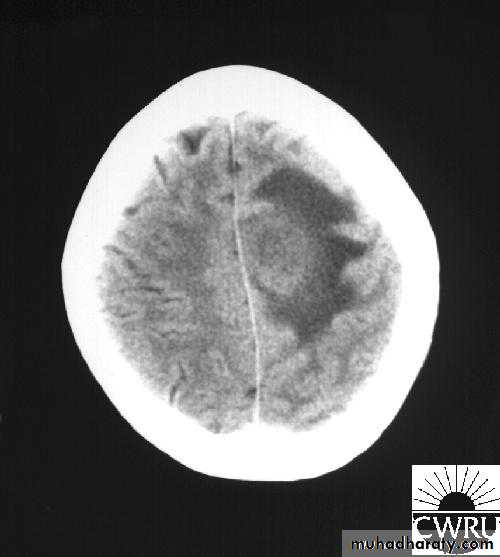

Brain Abscess CT without contrast